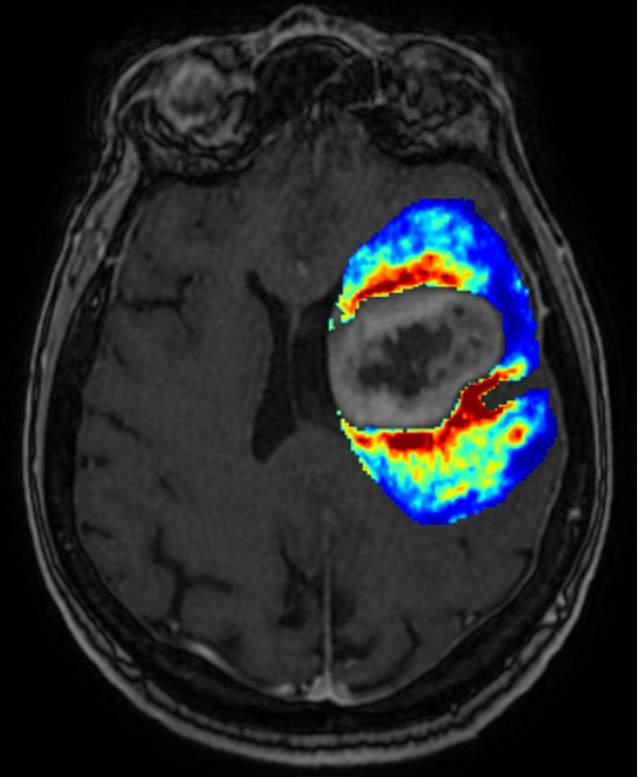

GlioMap is an innovative solution designed to predict areas of infiltration and subsequent recurrence in glioblastoma using radiomic features derived from multiparametric MRI.

This model leverages voxel-wise radiomic features extracted from the non-enhancing peritumoral region of glioblastomas on multiparametric structural MRI. It outputs the probability for each voxel to become a site of future tumor recurrence, visualized through color-coded maps.

Extending resection boundaries (supramarginal resection) has been shown to prolong survival. However, advanced imaging techniques like perfusion MRI, spectroscopic MRI, and diffusion MRI are not widely available to identify infiltrated regions or recurrence sites.

Currently, there is no precise boundary for supramarginal resection during surgery, and radiotherapy continues to rely on standard margins.